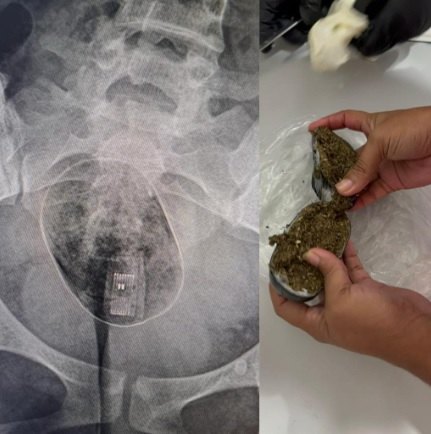

Na última quinta-feira (21), uma mulher foi levada ao Hospital Geral do Estado (HGE) após uma ousada tentativa de entrar no presídio Baldomero Cavalcanti, localizado no Complexo Prisional de Maceió, com pacotes de drogas e um pendrive inseridos em suas partes íntimas. A tentativa criminosa foi detectada durante a revista com o equipamento de bodyscan pela Polícia Penal, que identificou a presença de dois pacotes, um contendo substâncias ilícitas e o outro com um pendrive. A mulher conseguiu expelir o pacote com o pendrive, mas o segundo pacote permaneceu em seu corpo, necessitando de cirurgia para sua retirada.

Segundo informações da Secretaria de Ressocialização e Inclusão Social (Seris), a paciente foi inicialmente encaminhada à Unidade de Pronto Atendimento (UPA) devido à impossibilidade de retirar o pacote com drogas do seu corpo. Posteriormente, devido à necessidade de intervenção cirúrgica, ela foi transferida para o Hospital Geral do Estado.